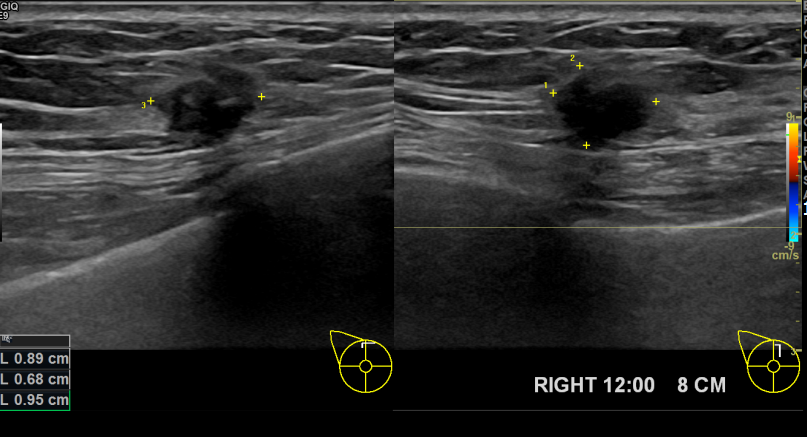

상기환자 외부건진상이상소견으로 내원하신 50대여성분으로 우측유방

의심스러운 혹 조직검사시행후 유방암 진단되었습니다